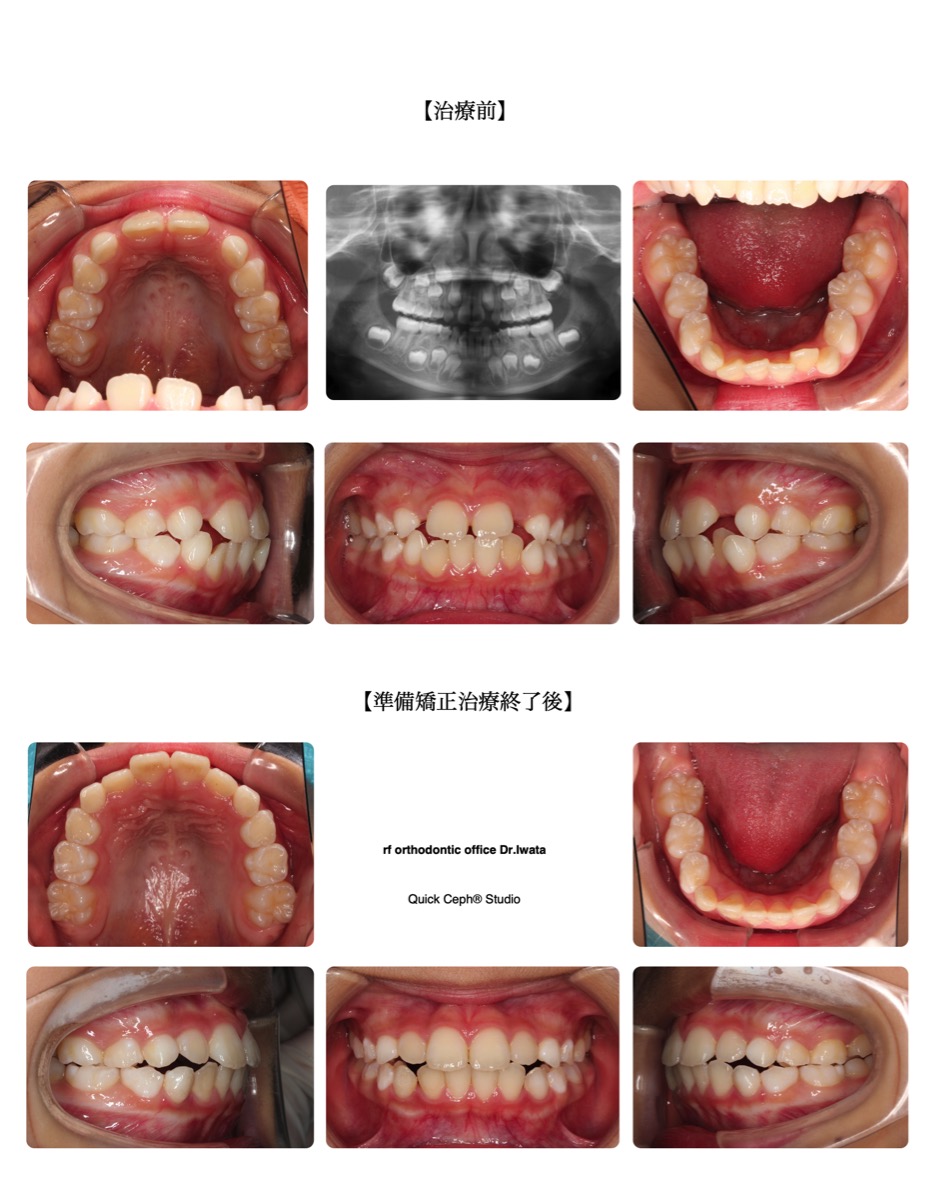

叢生症例 <切端咬合を伴う叢生に対する準備矯正治療>

上下の前歯がガタガタしている、いわゆる「叢生(そうせい)」に悩む方は少なくありません。今回の患者様は、上の前…